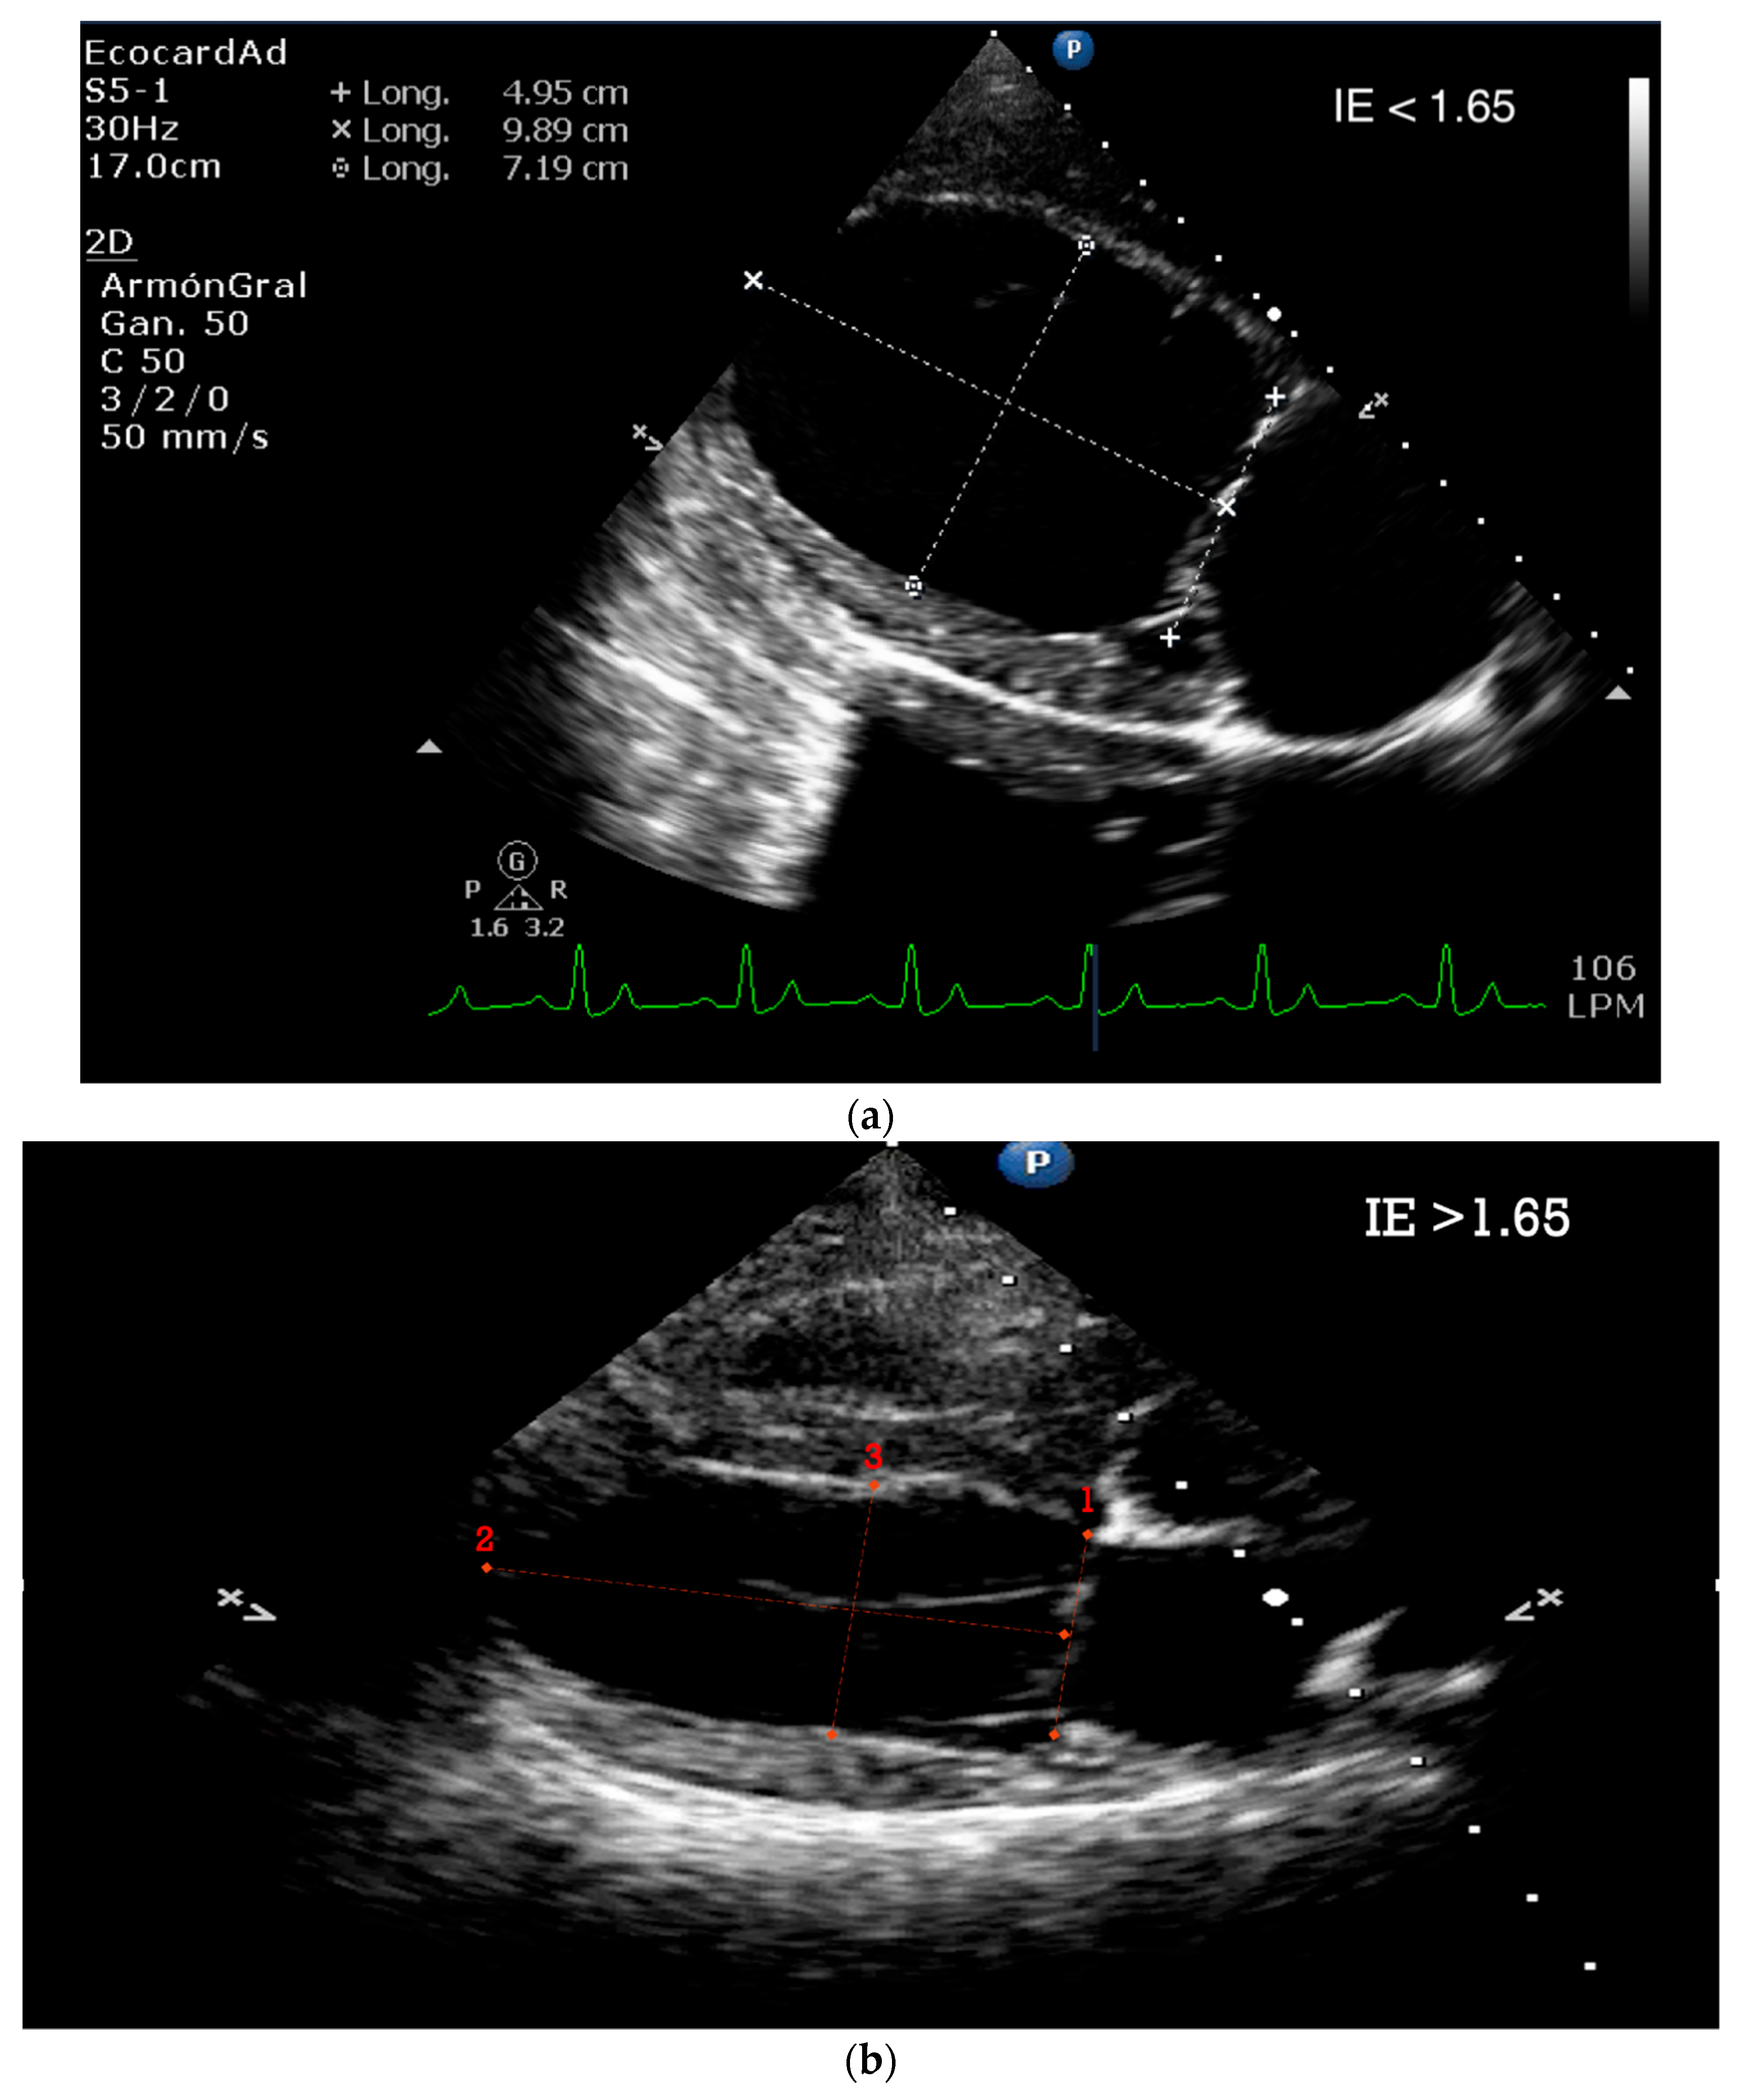

5.1.2. E-Point to Septal Separation or EPSS: An Echocardiographic Parameter for Accurate Assessment of Left Ventricular Performance

5.1.3. Sphericity Index (SI)